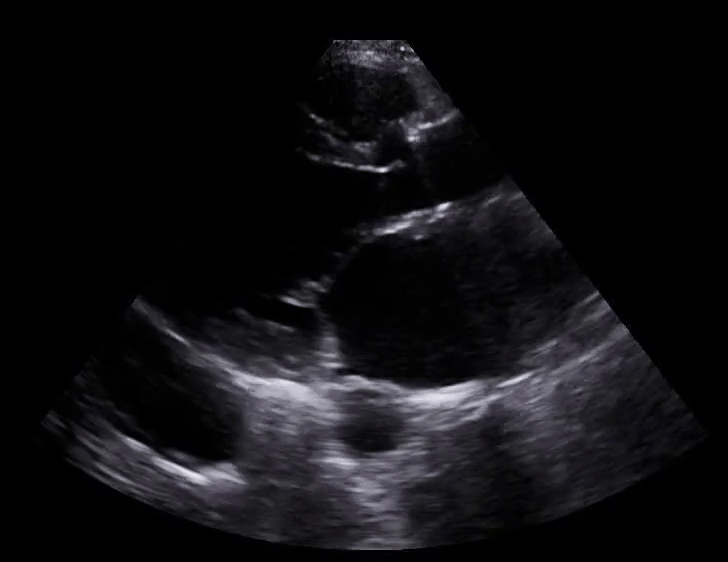

Scanning technique: When evaluating for intussusception with point-of-care ultrasound (POCUS), the infant is placed supine and a high-frequency linear transducer is used initially, with a curvilinear probe available for deeper or larger fields of view. The abdomen is scanned systematically in transverse and longitudinal planes, starting in the right lower quadrant and sweeping through the right upper quadrant, epigastrium, and left abdomen, with particular attention to the periumbilical region and right upper quadrant, where intussusception is most commonly identified. Graded compression is applied to displace bowel gas and improve visualization. On POCUS, intussusception classically appears as a “target” or “donut” sign in the transverse view, characterized by concentric hypoechoic and hyperechoic rings, and as a “pseudokidney” or “sandwich” sign in the longitudinal view. Associated findings may include proximal bowel dilation, free fluid, or absent peristalsis within the involved segment.